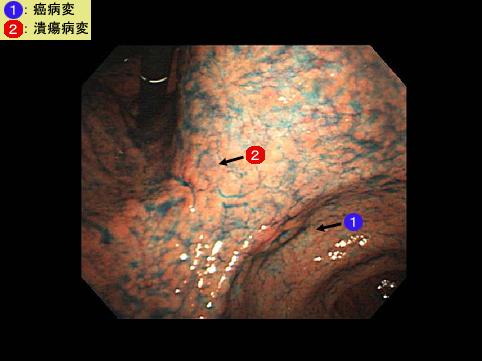

clasificación del pacienteTumor Epitelial Maligno/Cáncer a células en Sello de Anillo

parte(separada por órganos)estómago(región)/ángulo

método de exámenEndoscopia

clasificación ectoscópica de tumoresTipo 0(tipo superficial)/Tipo III(III+IIc)

diámetro mayor del tumor10 - 14

grado de penetraciónsm